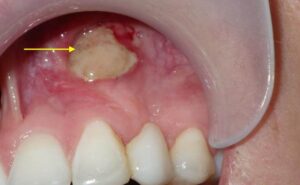

• رؤية جزء أبيض اللون أو صلب تحت اللثة

• تورم غير طبيعي أو التهاب في اللثة في منطقة معينة

بعد خلع السن أو جراحة الفم

أحد الأسباب الأكثر شيوعًا هو ما يحدث بعد خلع السن، حيث إذا لم تتكون جلطة الدم بشكل صحيح أو بقيت قطعة من الجذر، يظهر عظم الفك. أحيانًا يؤدي ارتشاف عظم الفك (resorption) إلى انحسار اللثة وبروز العظم.